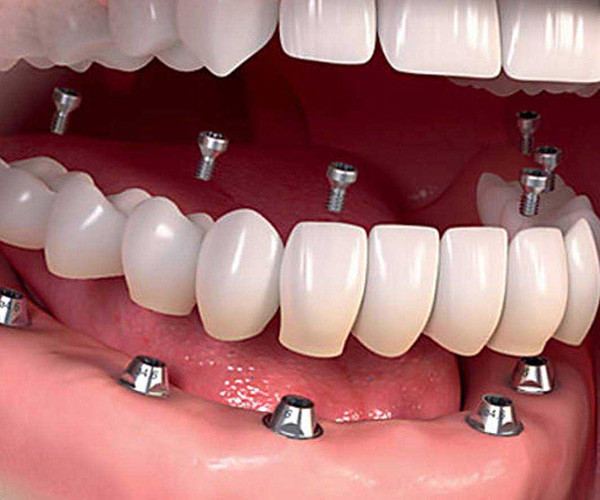

Permanent dental implants are made with metals like titanium or zirconia. They are embedded well into the gum line and act just like the roots of your teeth. Replacement teeth are then affixed onto these implants. Dental implants can last a lifetime and are considered to be a permanent solution for tooth loss. All-on-four and all-on-six dental implant surgeries can be done to give you a new set of teeth in just one jaw or your entire mouthful of teeth.

How many implants are needed for a full mouth?

Dental Artistry offers the option of giving you a full set of teeth with just four sets of implants. This surgical procedure is called all on four. One implant can hold in place multiple teeth. Sometimes your dentist may recommend that you have six implants instead of six, this is called the all on six procedure. Your dentist will advise how many implants are best for your needs.